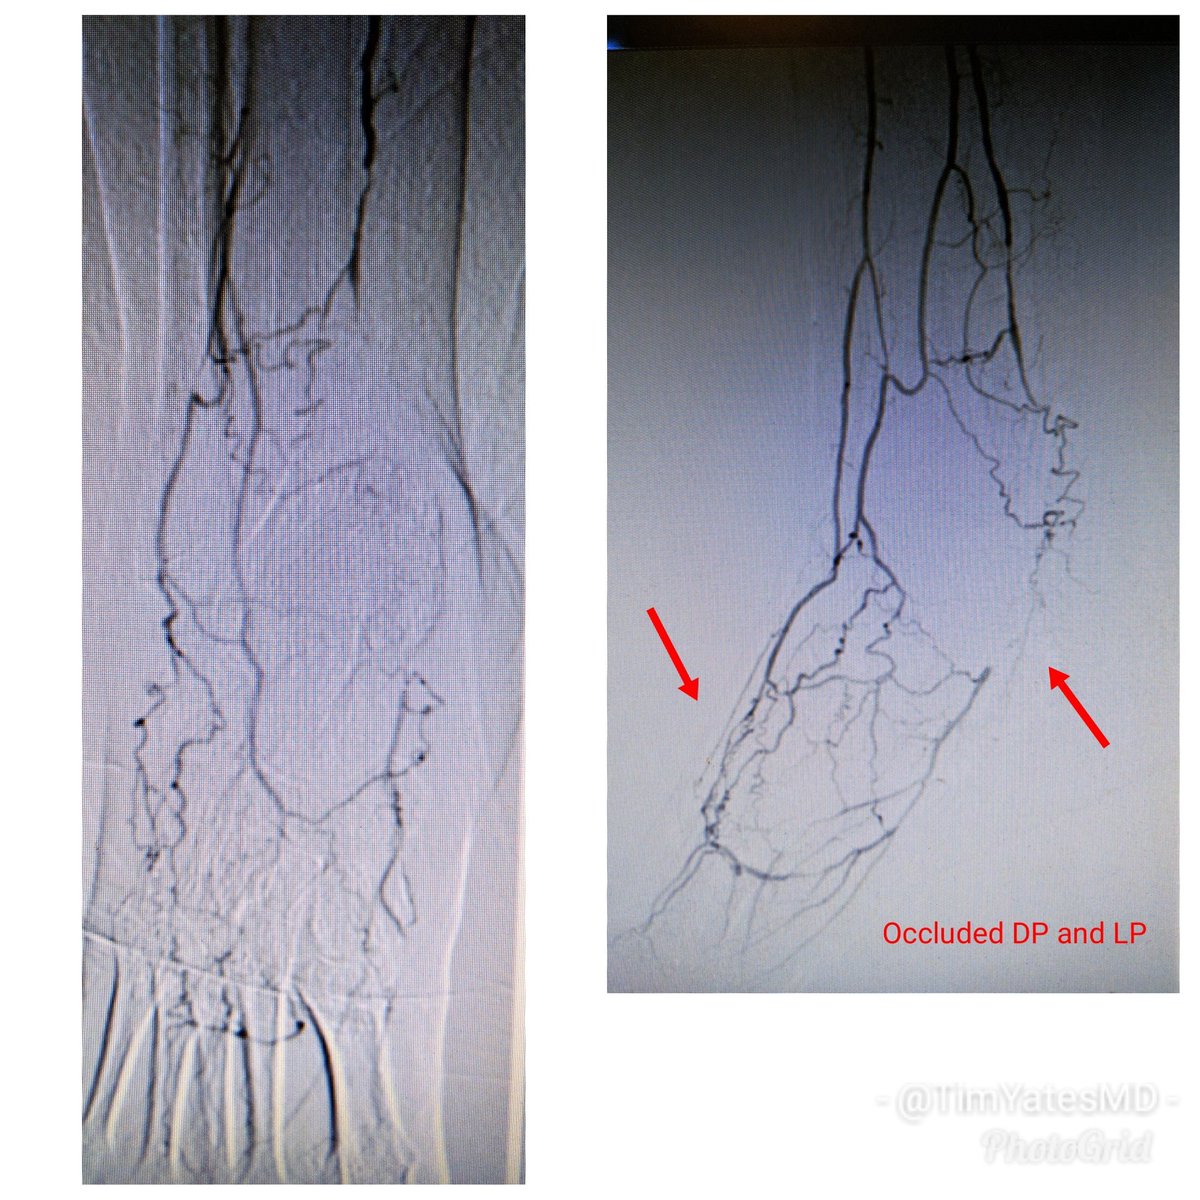

62 y/o F DM (HgA1c 14), plantar foot wound, OM of met head RC6 #CLI. #CSI @AbbottGlobal #commandwire #asahiregalia #POBA #Stopthechop #CLIfighters @Mustapja @FadiSaab17 @drsavealimb @SriniTummala @BOlivieriMD @DrBTKatzen @DrBobBeasley @keithppereira @kmadass @SDhandMD @JVIRmedia